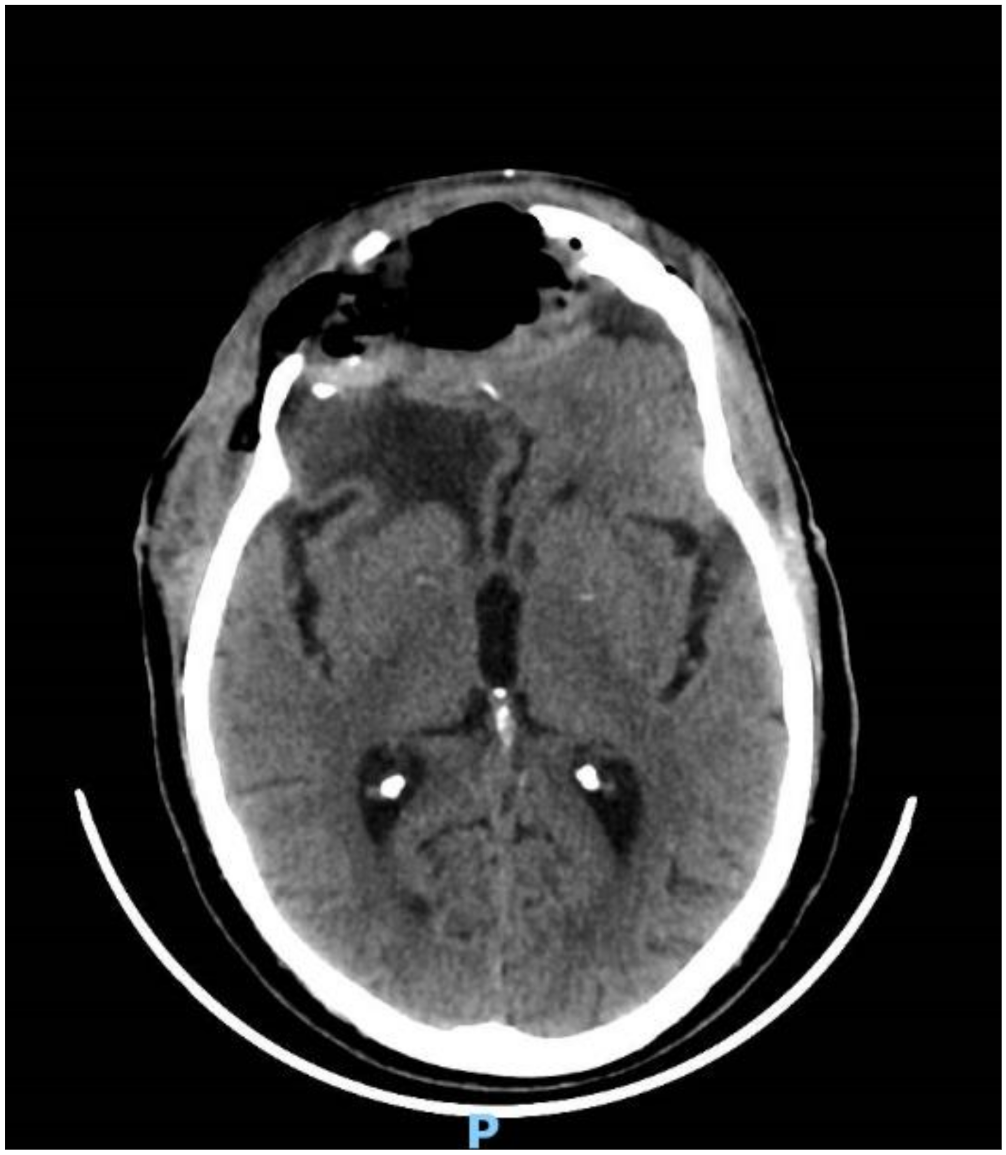

2. Case Report